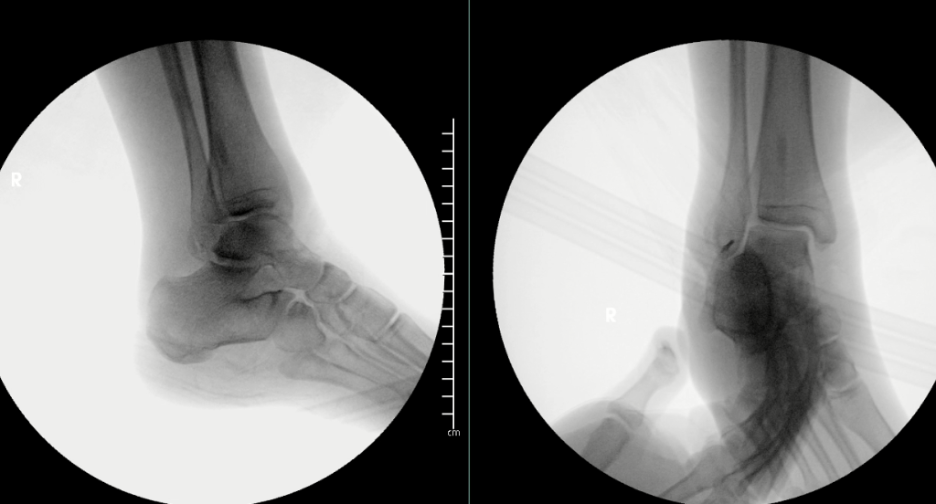

One should obtain plain film radiographs in the emergency department (Figure 1 above) prior to reduction and then following reduction. Multiple postreduction views should confirm proper position of the tibiotalar, subtalar, and talonavicular joints. Following reduction, computerized tomography (CT) scans may assist in identifying any residual intra-articular debris or articular irregularities.6,7 Additionally, one should consider CT results prior to taking the patient to the operative suite. Additionally, 3D-reconstructed CT scans may help scrutinize reduction and aid in surgical planning (Figure 2 below).

Plain film X-ray images (Figure 3 above) showed a pantalar dislocation at the subtalar (STJ), talonavicular (TNJ), and tibiotalar joints. The posterior portion of the fibula demonstrated a fracture. Computed tomography showed osseous debris in the posterior facet of the subtalar joint.